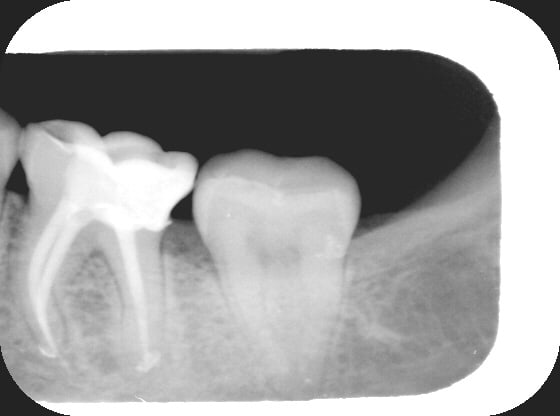

tu peux me confirmer que la première radio de ton ami yves est bien une prémolaire sup à trois racines bien séparées (je crois qu'il y a des canaux accessoires dans le palatin) et la technique d'obturation qu'il utilise ? par avance merci

en général entre une canine et une deuxième prémolaire sup, c'est bien une première prémolaire qui se trouve. et elle a bien 3 canaux.

et la technique d'obturation est de la condensation verticale de gutta à chaud.